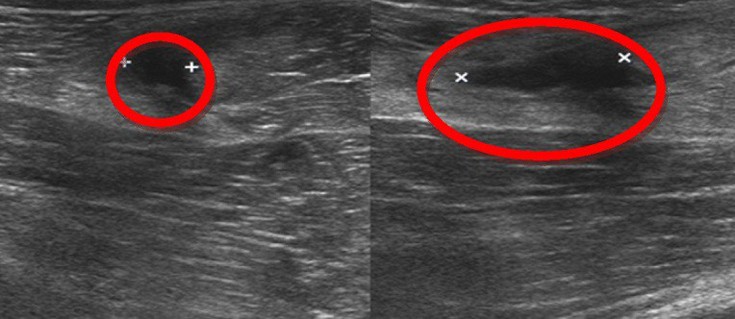

Πώς ελέγχεται